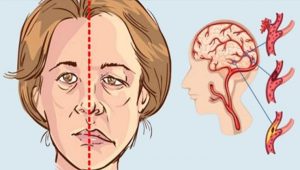

Como saber se uma pessoa está a ter um derrame! Pode fazer toda a diferença! E o que fazer para se prevenir!

O derrame, também conhecido por acidente vascular cerebral (AVC), é uma das principais causas de morte no mundo inteiro. Ele divide-se em dois tipos: